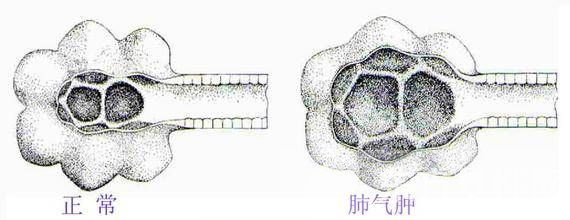

肺气肿是指终末细支气管远端(呼吸细支气管、肺泡管、肺泡囊和肺泡)的气道弹性减退,过度膨胀、充气和肺容积增大或同时伴有气道壁破坏的病理状态。按其发病原因肺气肿有如下几种类型:老年性肺气肿,代偿性肺气肿,间质性肺气肿,灶性肺气肿,旁间隔性肺气肿,阻塞性肺气肿。

在正常的呼吸中,肺泡扩张后收缩,使氧气进入血液,并且把二氧化碳排出。患上肺气肿之后,肺泡失去弹性,为了代替,就过度扩张,以致破裂,因而减少了氧气的摄入量。这样一来,心脏及颈、胸、腹部与呼吸有关或控制呼吸的肌肉必须更加用力地工作,以便摄取足够氧气。此外,患者的两肺膨大,从侧面看上去有桶状胸。肺气肿病情进至严重阶段,患者持续缺氧,同时过量的二氧化碳积聚在体内。患者须要借助医疗措施来改善呼吸,包括使用机械辅助呼吸与面罩吸氧。最后,患者的呼吸功能可能完全衰竭。